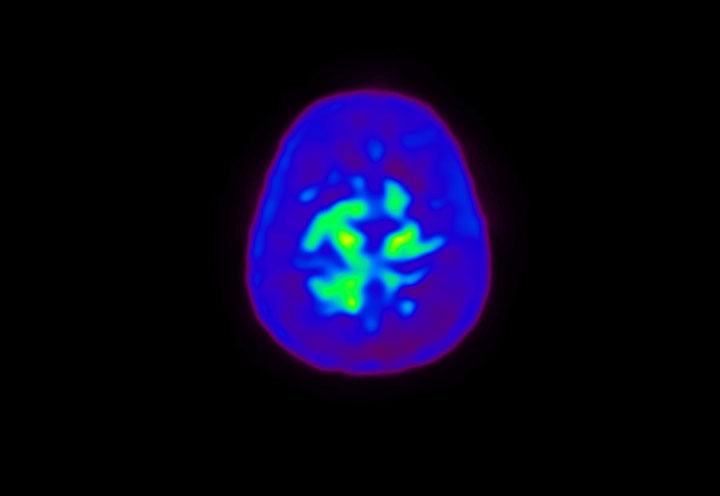

Head / Case4 : Amyloid

Axial

Courtesy : Kindai University Hospital

- Injected dose: 3.21 MBq/kg, 18F-Flutemetamol

- Uptake time: 100 minutes

- Scan time: 20 minutes